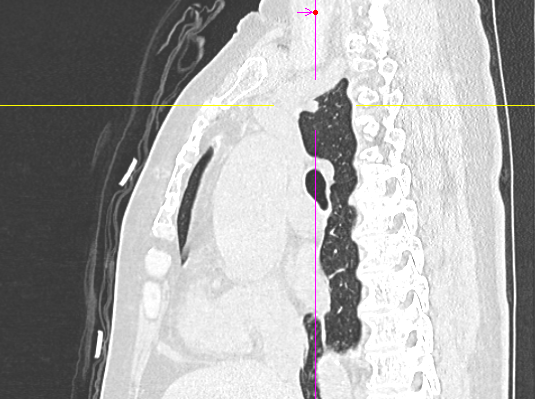

数月前,66岁的龚女士在肺癌术后随访复查中,胸部CT报告显示其右上肺新发实性结节一枚,并由刚开始发现时的5mm逐步增大至10mm。更棘手的是,这个结节位于右肺上叶尖段的纵隔胸膜下,位置极其“刁钻”。面对这份报告,患者龚女士陷入了深深的焦虑。因为其7年前因右中肺肿瘤行右中肺癌根治术,对于新发的实性结节为何种性质,是新发肺恶性肿瘤或是良性病变,亦或是原肺癌复发转移,目前均不能明确。辗转多家医院,得到的建议多为“定期观察,等待变化”或考虑创伤较大的传统穿刺活检,但结节位置非常深,单纯CT引导下定位穿刺很难精准到达,且需穿行的肺组织较多,创伤较大。

经过团队讨论,一个优化解决方案被提出:启用科室引进的前沿技术——电磁导航支气管镜系统。手术当日,在磁导航的实时引导下,手术团队娴熟地将吲哚菁绿注入目标结节区域,完成了对病灶的精确标定。整个过程患者无任何额外创伤,几乎零出血。

定位完成后,手术进入第二阶段。团队并未在患者胸部留下多个孔洞,而是仅在其肋间开创了一个长约3厘米的单一操作孔。通过这个“钥匙孔”,高清荧光胸腔镜顺利进入。在之前定位的明确指引下,手术团队迅速而准确地找到了这个深藏不露的结节,精准实施了“肺叶部分切除术”。

马主任解释系统原理:“这套系统就像为我们医生的操作装上了‘肺部GPS’。它通过术前将患者的CT影像数据导入系统,构建出独一无二的肺部三维‘地图’。术中,在磁场的引导下,我们操控一根细如发丝的导航探头,经由患者的口腔、气管这一自然通道,毫无创伤地直达常规支气管镜无法到达的肺外周深处,精准地停靠在目标结节旁边。磁导航支气管镜的优势是决定性的。它实现了‘经自然腔道、无创抵达’,彻底避免了经皮穿刺可能引起的高达20%-30%的气胸风险,为定位深部结节提供了安全、精准的解决方案。”